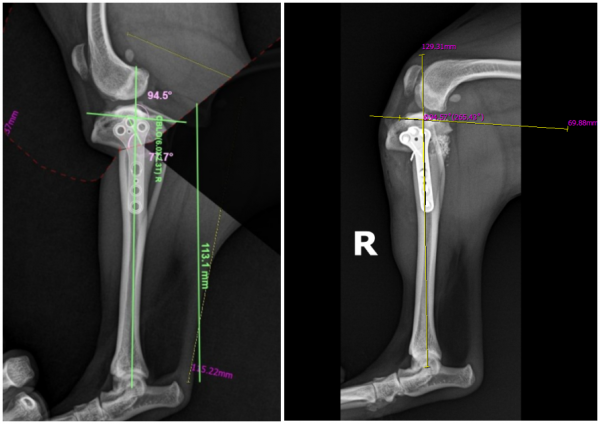

이후 예비 수술 프로그램을 이용해

가상의 환경에서 실제 수술을 시뮬레이션하며

안전하고 정확한 수술 계획을 세웠습니다.

수술 후 영상검사

사실 보기에는 쉬워보여도 주변에 근육과 인대가 많아서

정확히 수술하는 것은 매우 어려웠습니다.

그러나 수술 후 영상검사 시 정확하고 완벽하게 수술이 된 것을 확인할 수 있었습니다.